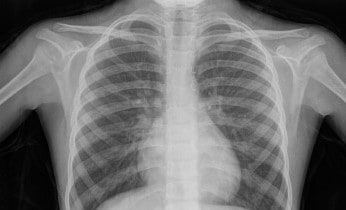

X-ray

X-rays is a type of radiation that is like light waves but are invisible and are higher in energy.

An X-ray machine produces short bursts of X-rays that pass through the squishy bits of your body (like soft tissues such as muscles and fluids like the food in your tummy and wee) but are blocked by dense tissue such as bones… oh, and objects like keys that shouldn’t be there!

You will be asked to lie on a table or stand against a surface so that the part of your body being X-rayed. A radiographer will show you where to position yourself to ensure the best image is taken.

The part of your body that needs to be imaged is then exposed to X-rays for a fraction of a second. The X-rays hit the a negative plate (like an old film camera) or are captured by computers.

You have to keep still for a moment or two so the image is clear and not blurry, whilst they click a button and it’s all done! X-rays are painless and you cannot see or feel them.